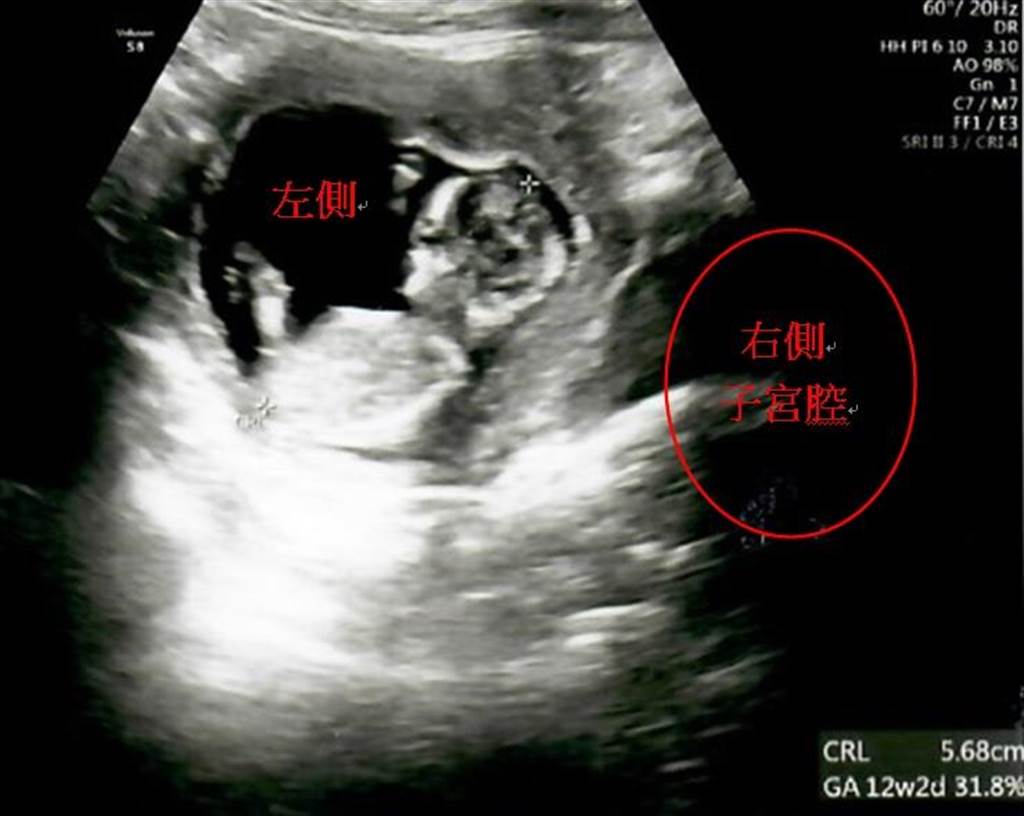

陳忠義解釋,生殖系統異常的婦女不是完全無法自然受孕,只要卵巢功能正常、排卵規律、輸卵管通暢,就有機會自然受孕;而陳小姐2年前來自茂盛醫院求醫時,透過超音波檢查也發現2個子宮腔的大小相近,所以在進入試管療程之前,先採行「陰道中隔切除術」,將夾在2個陰道中間約0.3mm厚的肌肉纖維切除,讓雙陰道合而為一,這樣她和先生努力做人時,陰莖只會插入唯一的陰道,提高自然受孕率。